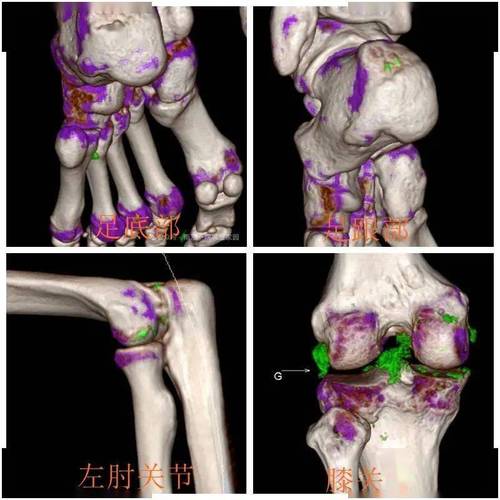

CT:CT扫描可以更清晰地显示尿酸盐结晶的沉积情况,对早期痛风诊断效果较好,CT扫描的成本较高,且辐射剂量较大,对患者的健康有一定影响。